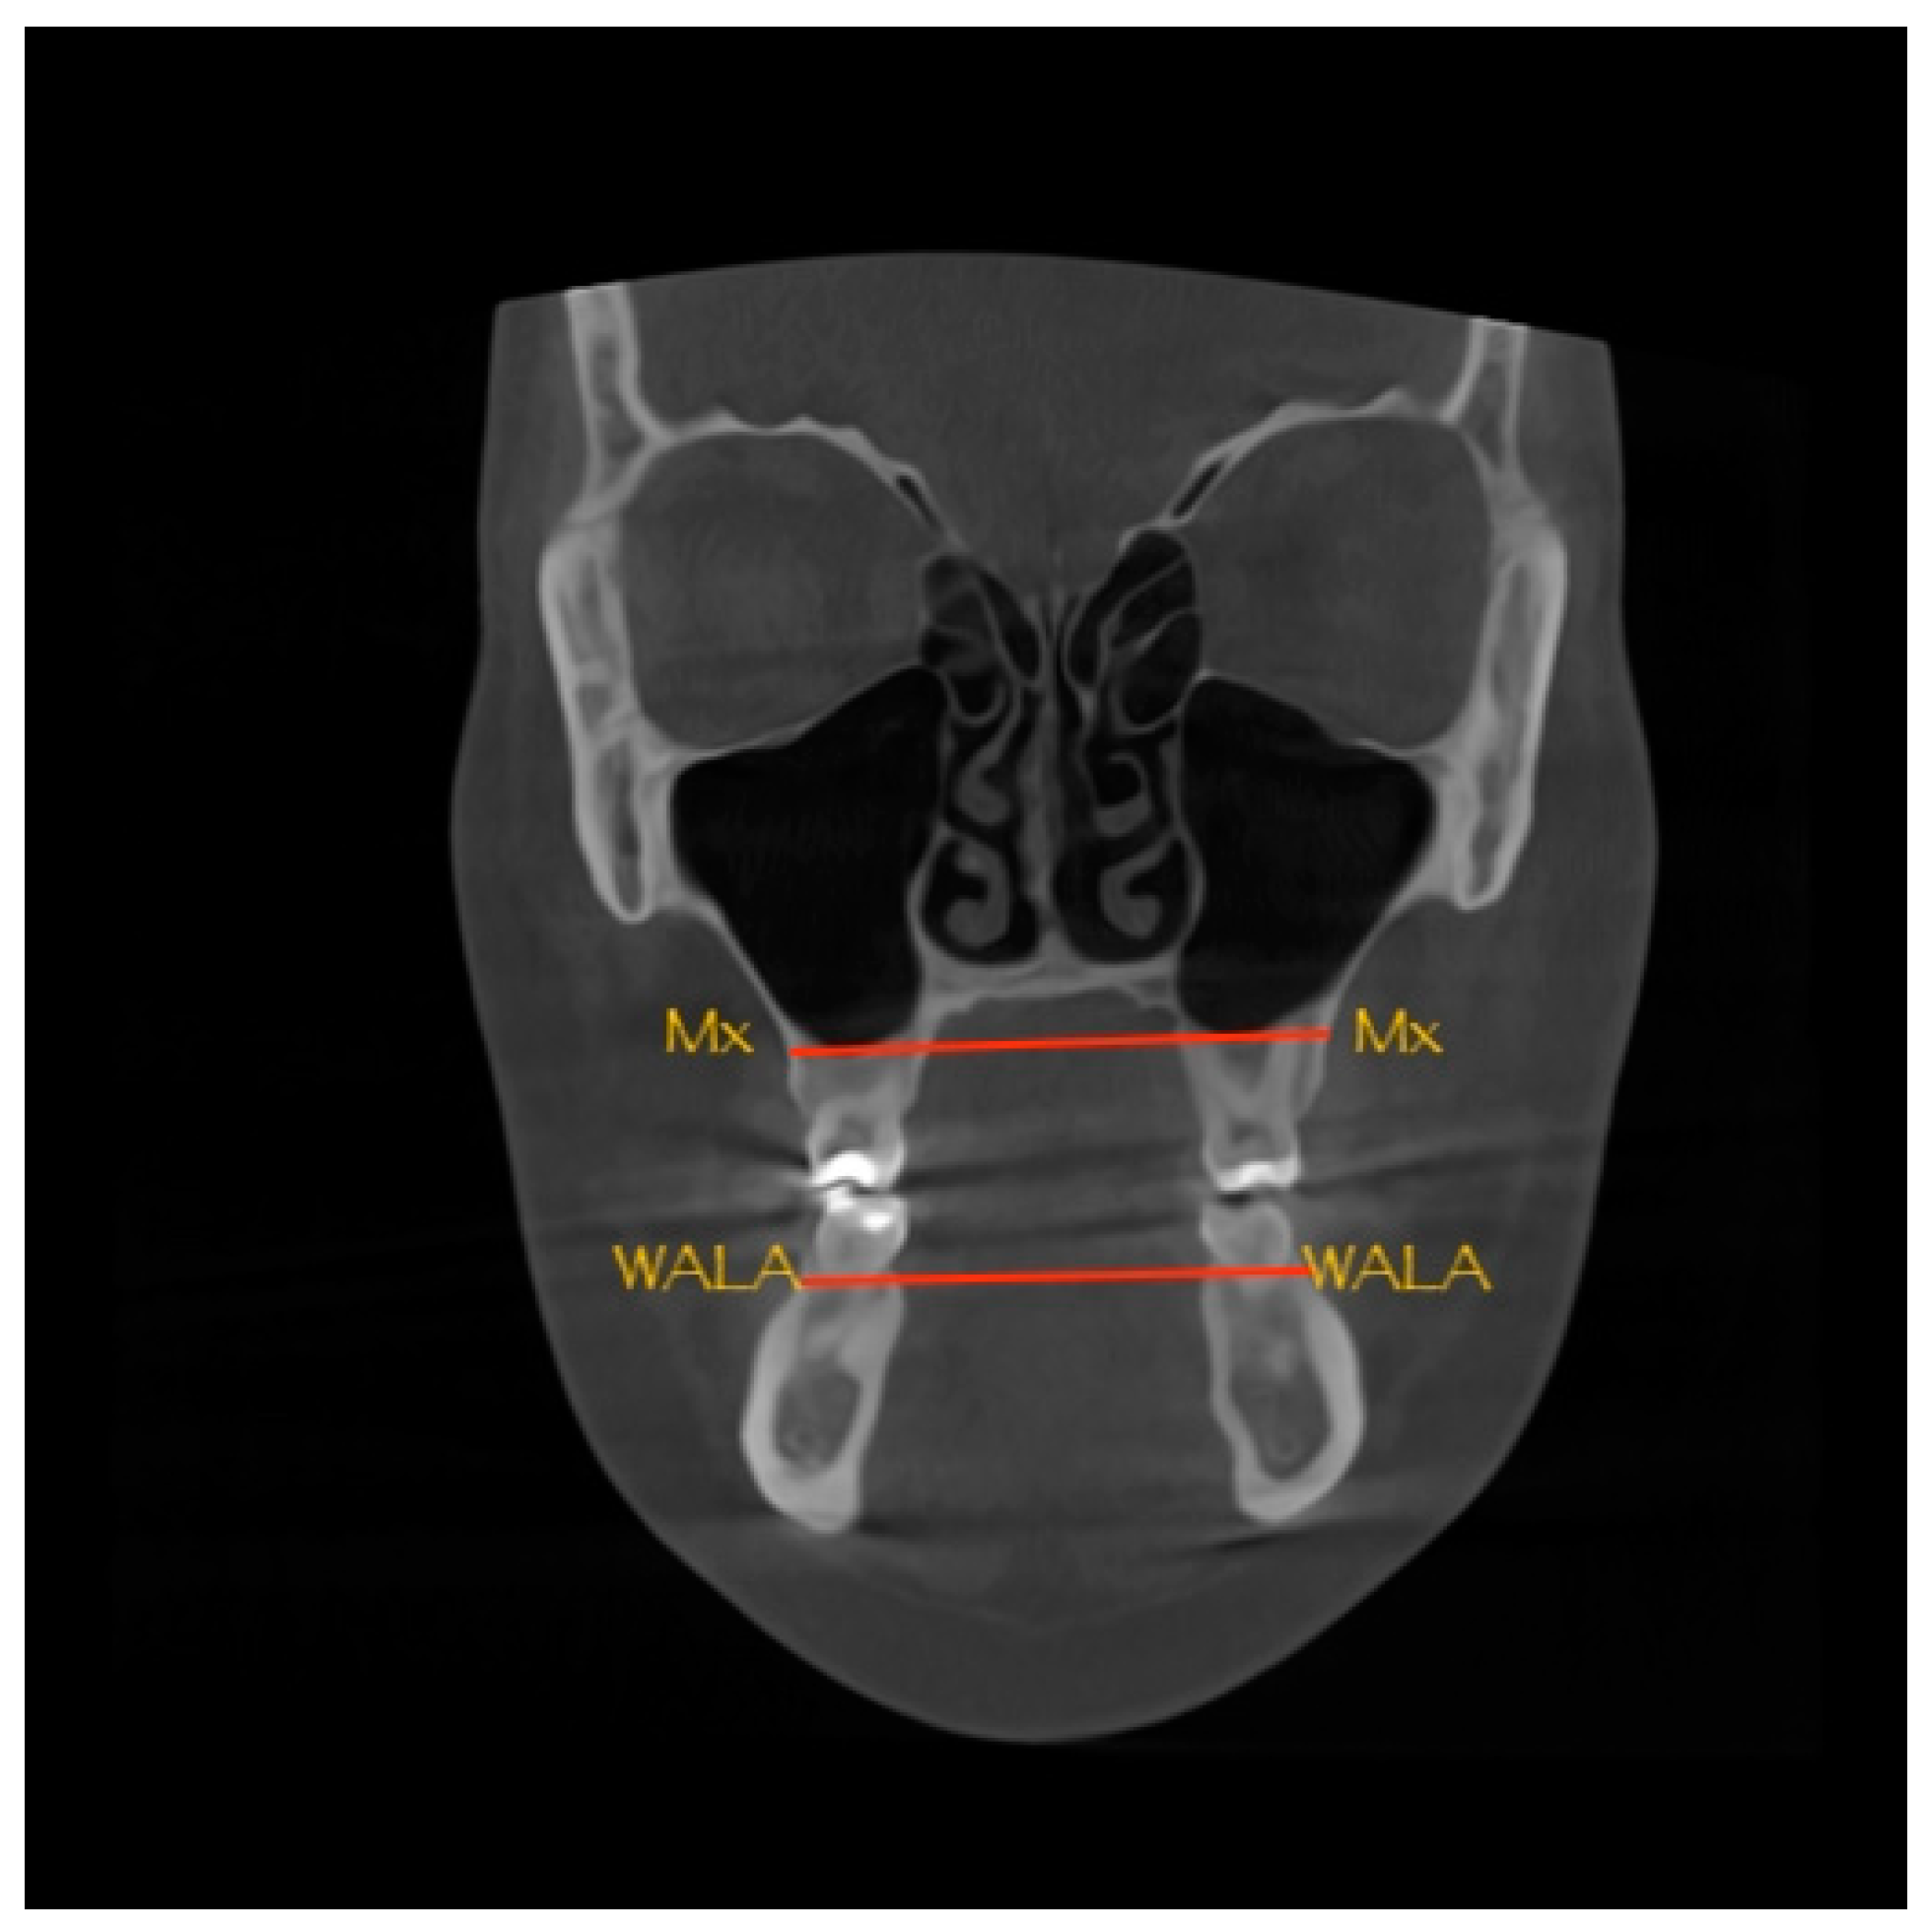

2. Materials and Methods